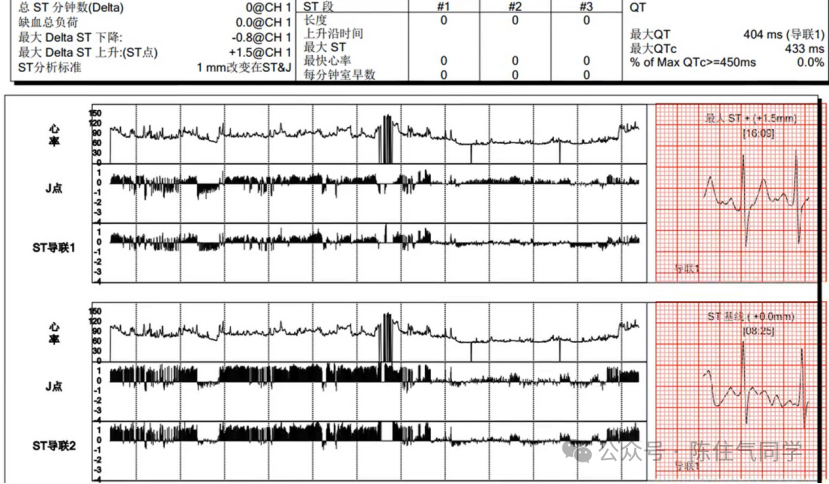

4ST段分析

可以观察 ST 段动态变化趋势图、发生的导联、ST 段抬高与下降的程度及其形态、ST 段移位持续时间、阵数等。

对于缺血的诊断,ST 段压低应至少 0.51.0 mV0.51.0 mm),在恢复至基线前至少持续 1 min次心肌缺血事件的时间间隔 ≥ 5 min

可计算出 ST 段下降总负荷(TIBST 段下降幅度 × 持续时间),TIB <60 mm·min/24 h70% 预后佳;TIB ≥ 60 mm·min/24 h,提示冠脉病变广泛,近期易发生急性冠脉综合征。